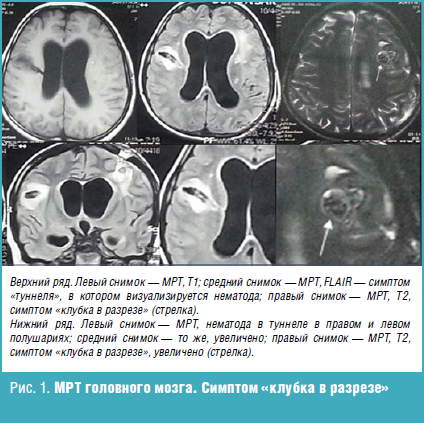

Нейроцистицеркоз и эхинококкоз что это такое - фото презентация